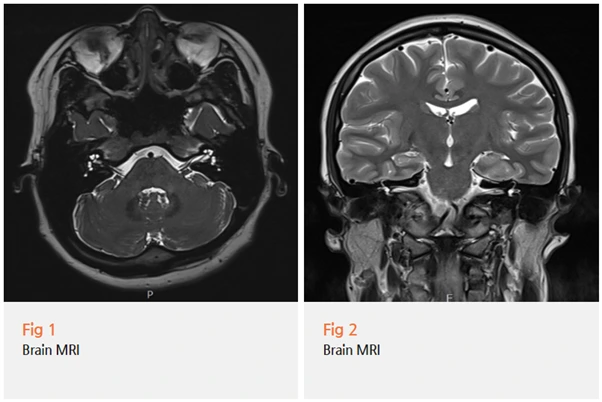

지금 바로 뇌 MRI 검사를 해봐야 할 것 같습니다.

✅ 필요시 뇌 MRI 검사

다행히 이 환자분의 경우,

MRI 검사 결과 뇌에는 아무런 이상이 없었어요.

벨마비로 확진할 수 있었죠.